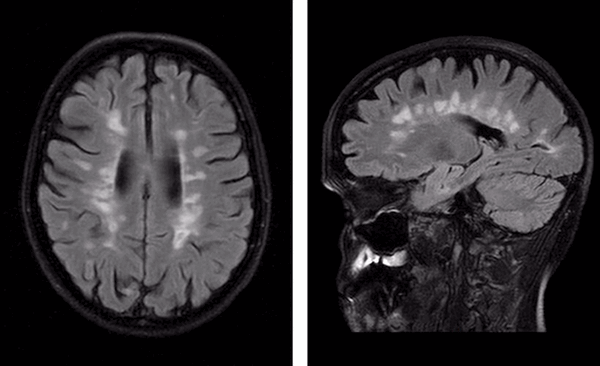

Стрелками на МР-томограммах отмечены участки демиелинизации нервных волокон. Слева - фото спинного мозга (сагиттальная проекция шейного отдела позвоночника), справа - головного (аксиальная плоскость)

Как выглядит рассеянный склероз на МРТ?

Диагностика рассеянного склероза позволяет выявить полную картину патологических изменений. Типичной считается следующая локализация очагов поражения:

- поверхностные отделы моста головного мозга;

- паравентрикулярное вещество, прилежащие к телам боковых и III и дну четвертого желудочков;

- средние ножки мозжечка;

- белое вещество под корой головного мозга;

- зрительный нерв;

- область шейного отдела спинного мозга;

- нижняя граница мозолистого тела.

Рассеянный склероз на МРТ головного мозга выглядит как пятна округлой формы диаметром до 2 сантиметров, которые по мере развития патологии могут сливаться. Оттенок измененных участков зависит от стадии болезни и бывает светлым, темным или идентичным здоровым тканям (без контраста не выделяется).

“Пальцы Доусона” на МР-томограммах в аксиальной (слева) и сагиттальной (справа) проекциях - выглядят на Т1 ВИ как светлые продолговатые очаги

Классическим признаком рассеянного склероза на МР-снимках головного мозга являются бляшки линейной формы, располагающиеся перпендикулярно боковым желудочкам. Их называют “пальцы Доусона”.